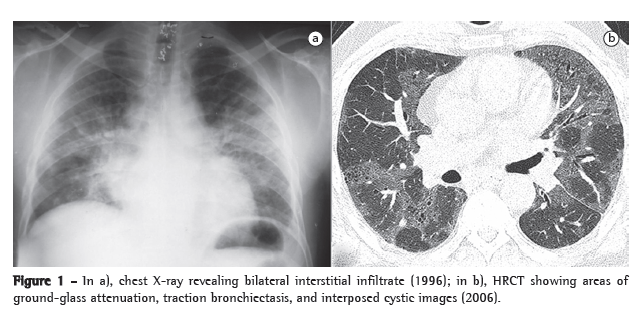

A 50-year-old male patient sought treatment at our facility. He had worked as an industrial plumber on an oil platform for 9 years and had been admitted to another hospital in 1996 for the investigation of dyspnea on exertion, mild productive cough, evening fever and arthralgia (all of which had started 5 years before that admission and had worsened 3 months prior). The patient reported having been treated for pneumonia on four occasions, with temporary improvement, had a history of systemic arterial hypertension and was a former smoker (20 pack-years) who had not smoked for 5 years. A chest X-ray showed bilateral interstitial infiltrate (Figure 1a); spirometry revealed signs of restrictive lung disease (FEV1 = 1.56 L [46.9% of predicted]; FVC = 2.01 L [51.2% of predicted]; FEV1/FVC = 77.9% [91.6% of predicted]); during the six-minute walk test, the patient presented a significant reduction in SpO2, which decreased from 96% to 87%; serology for HIV, hepatitis B and hepatitis C, as well as venereal disease research laboratory test serology, all yielded negative results; FAN = 1:160; and testing for anti-extractable nuclear antigen was negative. The patient was submitted to an open lung biopsy, which revealed desquamative interstitial pneumonia (Figure 2a), and started treatment for idiopathic interstitial pneumonia with prednisone at a dose of 60 mg/day for three months, the dose being tapered. The patient discontinued exposure after the onset of symptoms. He had no medical evaluations between 1998 and 2005, when he sought treatment at the interstitial disease outpatient clinic of our hospital. He was not using any medication, and his pulmonary function had worsened. Physical examination revealed fine crackles in the lower and posterior thirds of both hemithoraces. An HRCT scan showed ground-glass attenuation and weak interposed honeycombing (Figure 1b). The requested review of the slide of the lung biopsy detected the presence of giant cells (Figure 2b). When asked about occupational exposure, the patient revealed having worked as an oil industry plumber, during which time he often assembled tubing using tools (grinders, sanders) containing disks made of hard metal. He reported that those disks became blunt with use and needed to be sharpened, and that his only protection was a visor. He performed this activity, almost continuously, at least five days a week from 1982 to 1991, when the symptoms began. At that time, a chest X-ray requested by the company physician revealed pulmonary infiltrate. The patient was instructed to take a leave from work and seek specialized help. Based on these data, the patient was diagnosed with hard metal lung disease.

The symptoms of hard metal lung disease are nonspecific: dry cough; progressive dyspnea on exertion; digital clubbing/cyanosis; chest pain; fatigue; and weight loss.(7,8) Chest X-rays reveal a diffuse reticulomicronodular pattern, occasionally accompanied by lymph node enlargement, and, in the advanced stage of the disease, can show small cystic formations.(9) An HRCT scan can show areas of bilateral ground-glass opacity, areas of consolidation, extensive areas of reticular hyperattenuation, and traction bronchiectasis-findings that indicate fibrosis.(9,10) Other findings include honeycombing, centrilobular nodules, and emphysema.(7) Pulmonary function testing reveals restrictive lung disease.(8) The histopathological pattern can show desquamative interstitial pneumonia and giant cell interstitial pneumonia, with or without bronchiolitis obliterans, and a variable degree of interstitial fibrosis.(11)